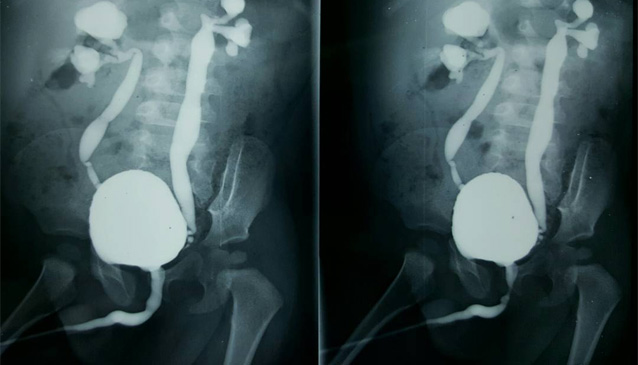

- Se instala una sonda fina a través de la uretra en la vejiga, que permite introducir por goteo un contraste hidrosoluble hasta que el paciente orine, y se obtienen imágenes mientras la vejiga se llena, durante el llene y al finalizar la micción.

El procedimiento implica la inserción de una sonda de Foley en la «fosa navicular» que es el punto más amplio de la apertura de la uretra a nivel del glande masculino. A ese nivel se infla levemente el balón de la sonda con 1 a 2 ml de líquido. Ello es seguido por la lenta inyección de 30mL de contraste soluble en agua mientras se obtienen varias radiografías sencillas con la persona en posición oblicua al plano de la radiografía para poder observar la uretra en la imagen.2 El escape del contraste fuera de la uretra sugiere daño uretral (normalmente secundario a trauma pélvico) y es indicación para una intervención quirúrgica reparadora